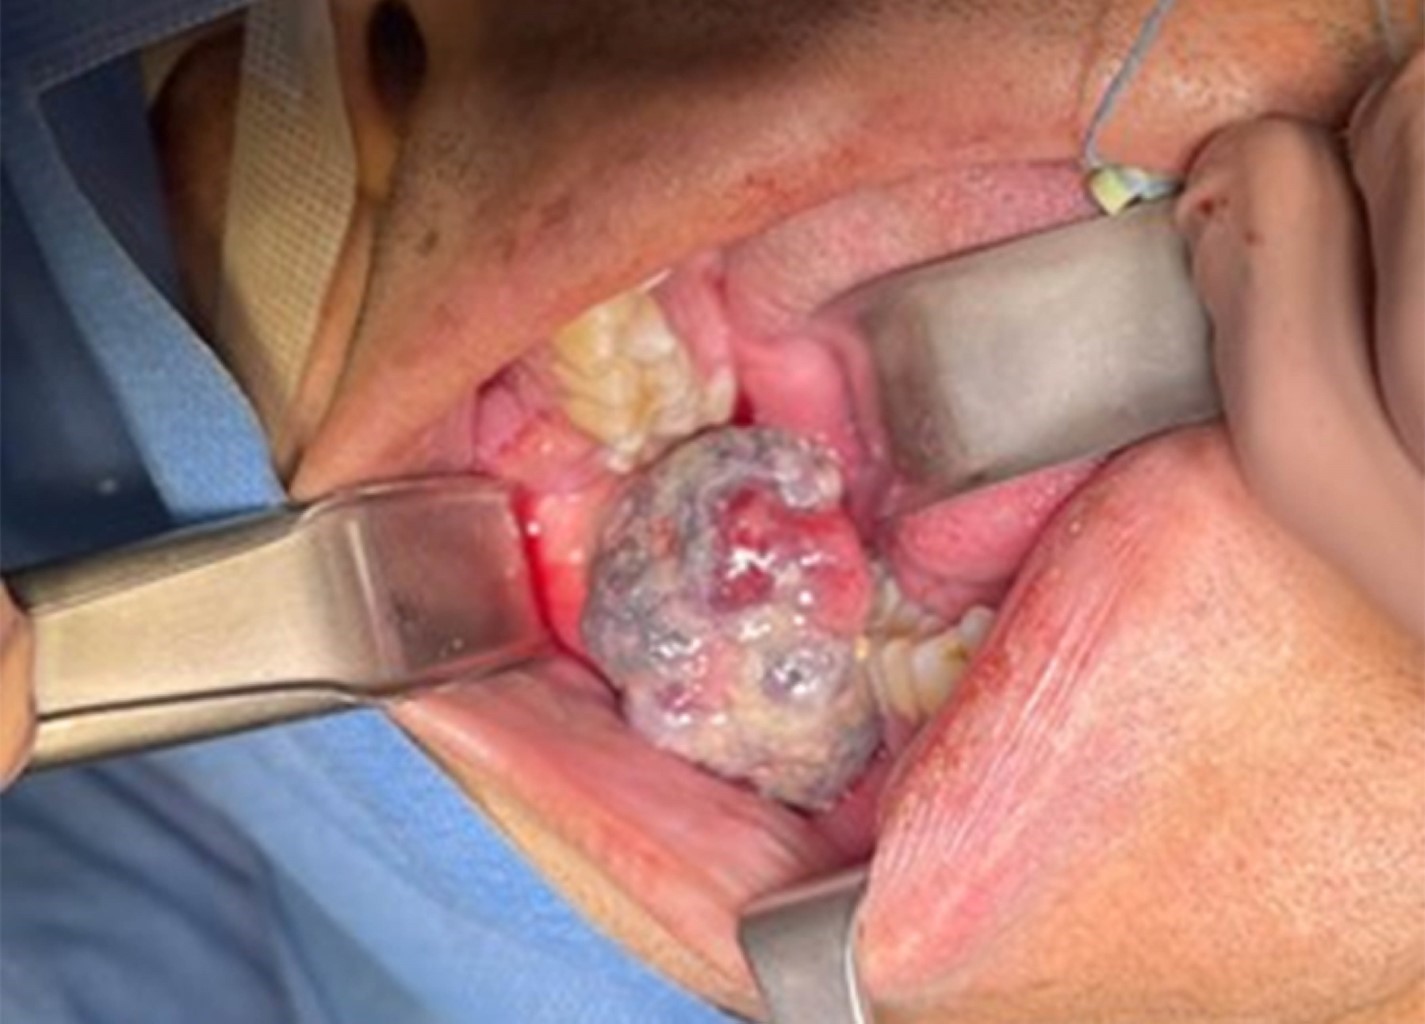

Es derivado desde un centro primario de atención médica por tumoración en región retromolar derecha, de 1 cm de diámetro, base pediculada, aspecto eritematoso y firme.

Se realiza biopsia incisional de lesión adyacente al diente 4.8 y unas semanas más tarde se confirma el diagnóstico histopatológico de granuloma piogénico (Figuras 1, 2 y 3). En ese momento se planifica exodoncia de los dientes 1.8, 3.8 y 4.8, junto con la exéresis completa de la lesión bajo anestesia general.

El 25 de mayo de 2025 se realizó el procedimiento exéresis de la lesión de más de 3 cm en relación a diente 4.8 (Figuras 4 y 5) bajo anestesia general sin complicaciones. En control del 23 de junio de 2025 se constata buena cicatrización y ausencia de recidiva. Se indica seguimiento periódico.